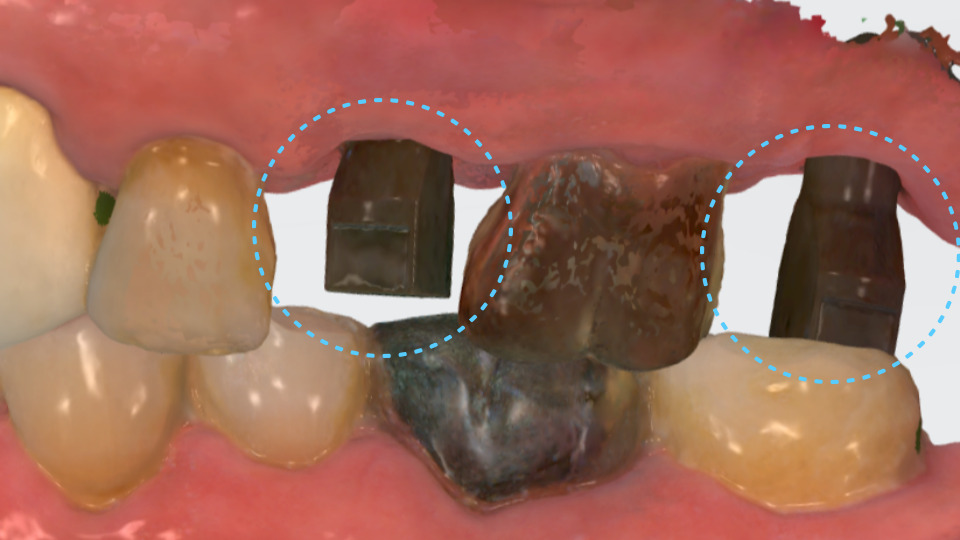

수술 후 약 4개월이 지나

충분한 회복이 되었기에

서울바르디치과는 크라운 작업을

착수하게 되었습니다.

과거에는 보철물을

만들기 위해 고무 인상재를

환자의 입 속에 넣고

본을 뜨는 과정이 필요했는데요.

서울바르디치과는

디지털 스캔을 활용해

좀 더 오차가 적고

편안한 진료 방식을

사용하고 있습니다.

잇몸 라인과 주변 치아까지

함께 정밀 스캔하기에

크라운을 만들 때도

정교한 활용이 가능한데요.

사진처럼 맞춤으로

연결 지대주(Abutment)를

제작해 음식물 끼임을

줄여줄 수 있습니다.